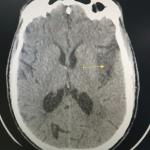

Cystite emphysémateuse

Une patiente de 89 ans, sans antécédent majeur, consulte aux urgences à la suite d’une chute accidentelle avec fracture...